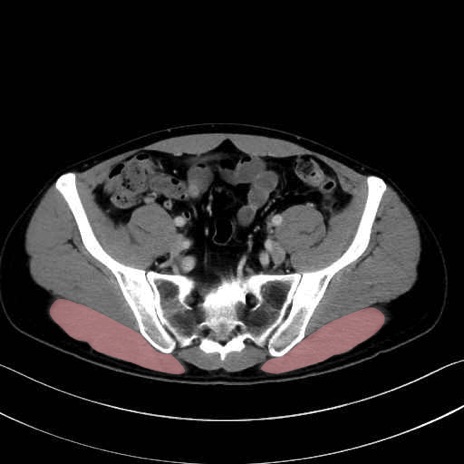

3. 殿部の筋肉(表層・中層・深層)

大殿筋 (Gluteus maximus)